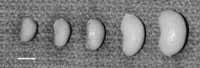

To increase the efficiency of the characterization of the interacting locus, a jck congenic line was generated that was homozygous for B6 alleles from D1Mit7 to D1Mit155 in a D2 background. When this D2.B6 congenic strain is crossed with B6jck/+ mice, and their progeny intercrossed, the congenic region is fixed as B6, whereas the remainder of the genome is segregating as an F2 population. In this experiment, all affected mice will be informative for the interacting locus and the genetic analysis will be much more efficient. One prediction for progeny of this intercross is that the distribution of PKD severity should be skewed to a more severe disease phenotype, since all of the mice are homozygous in the congenic region, rather than the one-fourth that would be in an F2 population. This is clearly the result, as shown in Figure 2 (mean: 1.53 g, variance: 0.76 g2, range: 0.41-3.8 g, n = 67). In many cases, the range in phenotypic variation was dramatic, even within the same litter, as shown in Figure 4.

Variation in affected kidney size. A single kidney from each of five affected F2 progeny obtained in one litter of a cross between B6 jck and D2.B6 chr1 congenic mice. Bar, 1 cm.